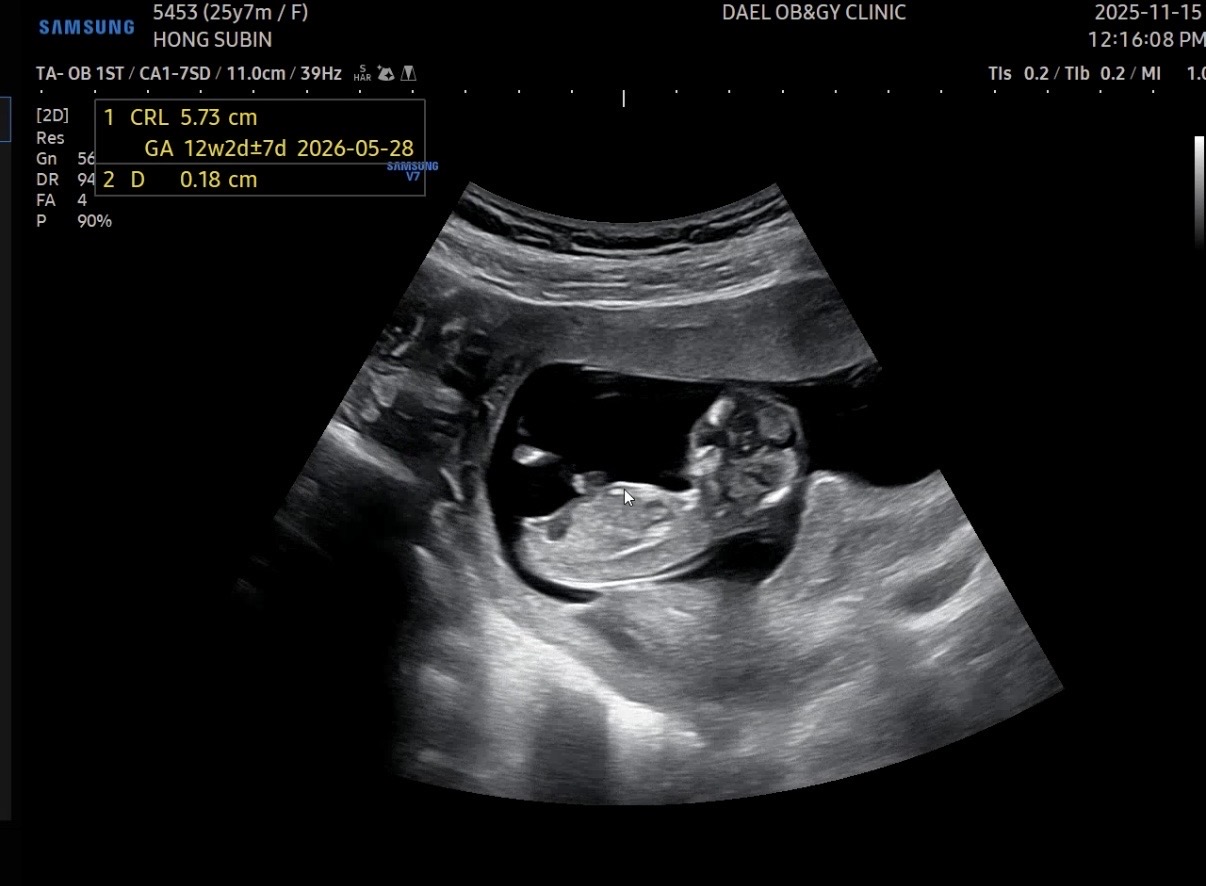

12주 0일 각도법 고수님들 봐주세요!!

각도법 봐주세요!! 빌리 ai는 같은 초음파 사진으로도 딸이랬다가 아들이랬다가 할때마다 왔다갔다 하네요.. 물론 각도법의 정확도는 낮다지만 자꾸 보게되어요 ㅋㅋㅋㅋ 고수님들 참견해주세요!! 댓글에도 사진 있어용

아이다리쪽이 다 안나와서 이건 어렵겠어요

아기가 다리까지 다 나온 사진은 이거밖에 없네요ㅠㅠ

아기가 다리를 모으고있네요ㅠㅠ